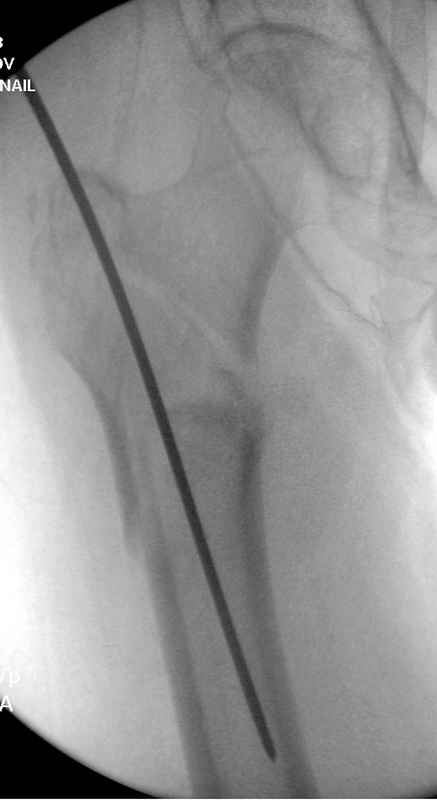

Здесь 83 года, травма в результате падения